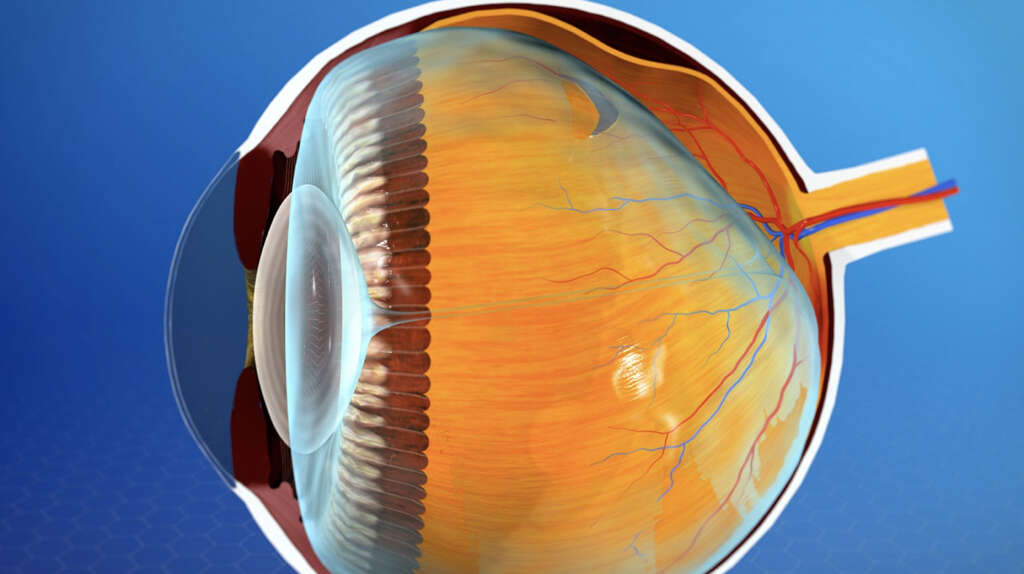

Изображения и анатомия сетчатки глаза

Раздел: Визуальный дайджест